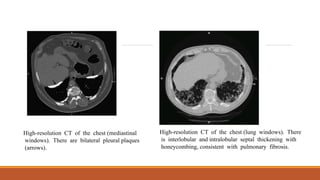

High-resolution CT of the chest (mediastinal

windows). There are bilateral pleural plaques

(arrows).

High-resolution CT of the chest (lung windows). There

is interlobular and intralobular septal thickening with

honeycombing, consistent with pulmonary fibrosis.

Initial investigations andfindings Chest X-ray showing indistinct cardiac borders and bilateral reticulonodular shadowing suggestive of pulmonary fibrosis.

High-resolution CT ofthe chest (mediastinal windows). There are bilateral pleural plaques (arrows). High-resolution CT of the chest (lung windows). There is interlobular and intralobular septal thickening with honeycombing, consistent with pulmonary fibrosis.